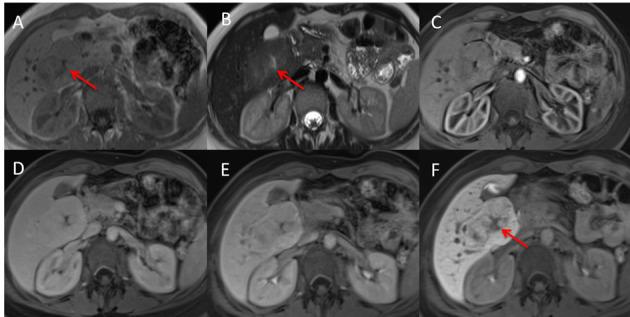

On computed tomography (CT) and magnetic resonance imaging (MRI), hepatocellular tumors are characterized based on typical imaging findings. However, hepatocellular adenoma, focal nodular hyperplasia, and hepatocellular carcinoma can show uncommon appearances at CT and MRI, which may lead to diagnostic challenges. When assessing focal hepatic lesions, radiologists need to be aware of these atypical imaging findings to avoid misdiagnoses that can alter the management plan. The purpose of this review is to illustrate a variety of pitfalls and atypical features of hepatocellular tumors that can lead to misinterpretations providing specific clues to the correct diagnoses.

在计算机断层扫描(CT)和磁共振成像(MRI)上,根据典型的影像学表现可对肝细胞肿瘤进行特征描述。然而,肝细胞腺瘤、局灶性结节性增生和肝细胞癌在 CT 和 MRI 上可能会出现不常见的表现,这可能导致诊断上的挑战。在评估局灶性肝病变时,放射科医生需要注意这些非典型的影像学表现,以避免误诊,误诊可能会改变治疗计划。本文旨在说明导致误诊的肝细胞肿瘤的各种陷阱和非典型特征,并提供正确诊断的具体线索。